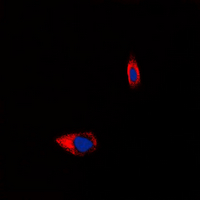

| WB, IF/IC |

| Dilution | WB~~WB (1/500 - 1/1000), IF/IC (1/100 - 1/500) IF/IC~~N/A |

| Cellular Location | Cell membrane; Multi-pass membrane protein. Early endosome {ECO:0000250|UniProtKB:P14600}. Note=After signaling cascade initiation, substance P binding results in receptor internalization and localization to early endosomes, followed by receptor recycling to the cell surface. {ECO:0000250|UniProtKB:P14600} |